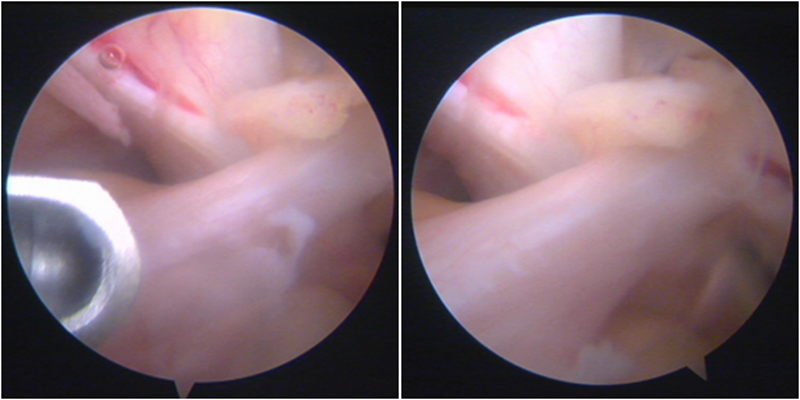

镜下显示ACL残束

内侧半月板

外侧半月板

股骨侧保残骨道建立

股骨侧骨道建立,椭圆形扩孔保残9mm

韧带导入过程

送止血带后韧带表明血管膜